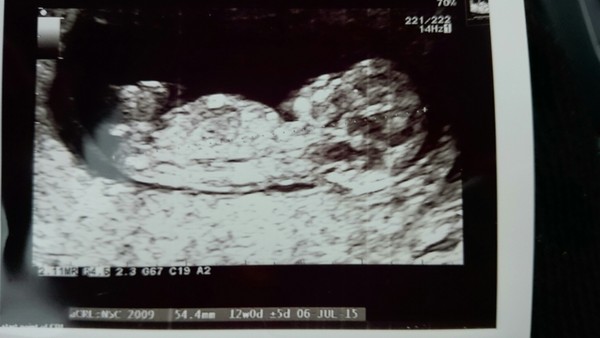

misseskimo · 22/12/2014 11:37

Hi Ladies,

Had my scan at the EPU this morning. All seems really well. Got an extremely wriggly munchkin in there! Was quite surreal if I'm being honest. Though at least we got good news which is all we wanted. She also re-dated me at 12wks which puts me a whole week ahead of her last measurement at 8wks. But she said they'll confirm at the official dating scan next week. In the meantime, she gave me another picture to take home for Christmas.

Thanks for all the support, means so much.

[pic attached]

Eskimo

Wow!! what an amazing picture!! I love it when they look like that, makes me all scan-broody Grin

misseskimo What a lovely scan picture! Much clearer contrast than mine. Glad to hear all is well Smile